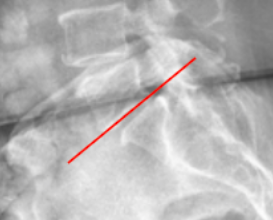

Ferguson’s Line